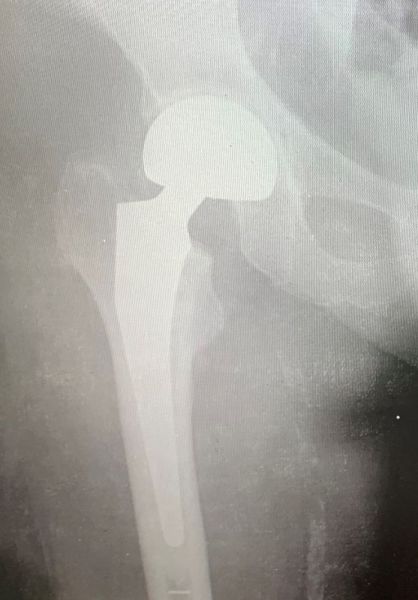

2. Comminuted extracapsular fracture of the left hip in a 69-year-old female.

Treatment: Nailing with a proximal femoral nail

I. Before surgery II. Post-surgery, x-ray showing the proximal part of the nail and the reduction of the fracture III. Post-surgery, x ray showing the distal part of the nail